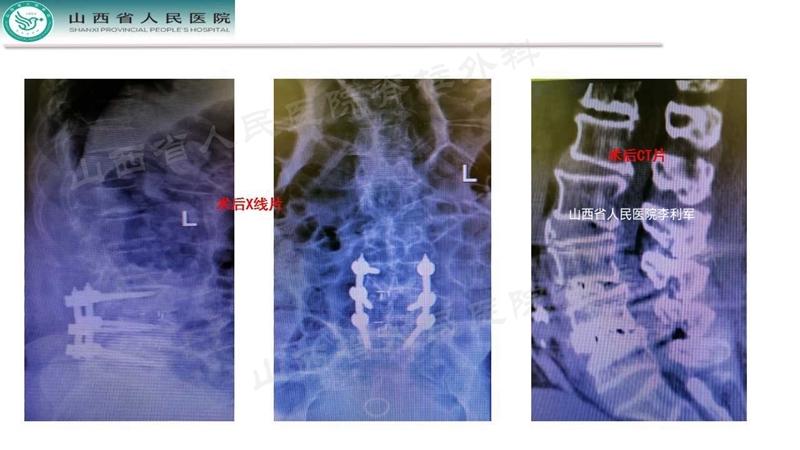

Case 3